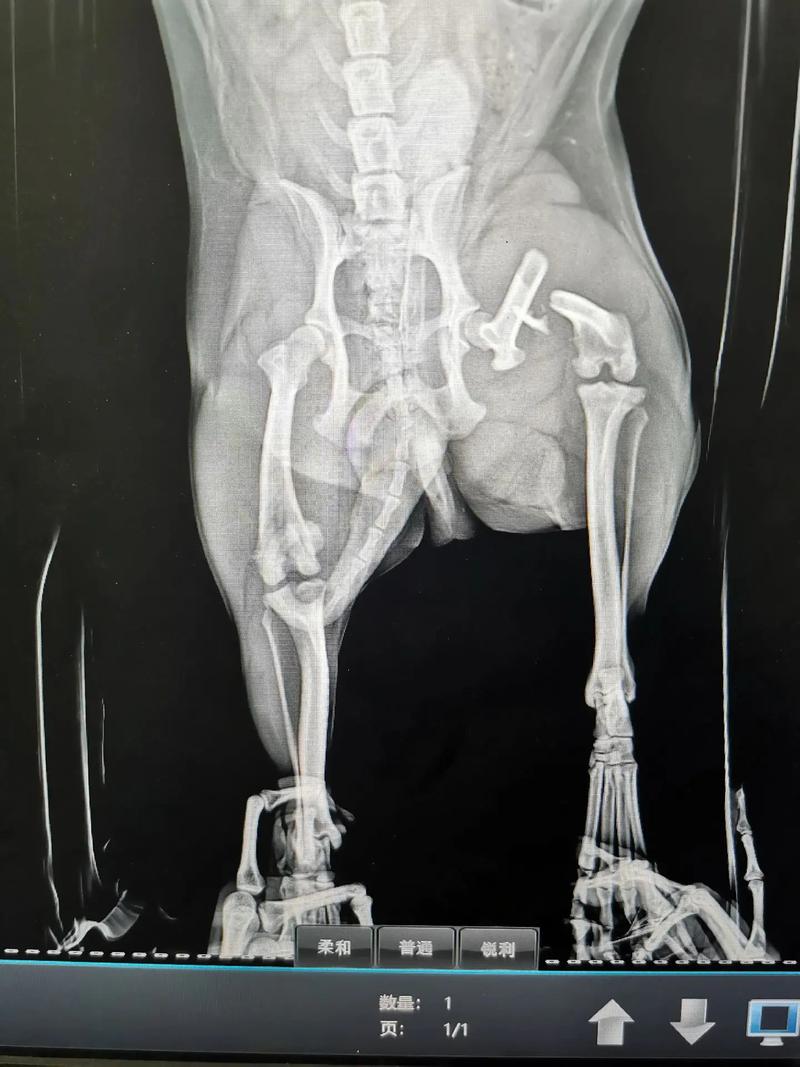

狗狗后腿韧带断了主要会出现后腿随意摆动、狗狗无法控制后腿运动、疼痛、无力等现象。狗狗后腿韧带断裂需要做核磁共振或者CT来确诊,如果狗狗的韧带确实断了,则根据狗狗的具体情况给狗狗做手术或者让狗狗静养让其自愈。

〖壹〗、因此,如果狗狗的韧带断裂影响到了它的正常活动和生活,建议还是考虑手术治疗。手术治疗可以通过重建或修复韧带来恢复膝关节的正常功能和稳定性,是近来最可靠和有效的治疗方法。

〖肆〗、如果狗狗后腿的十字韧带断裂,手术治疗是近来最可靠和有效的治疗方法。非手术治疗方法包括使用石膏固定、理疗、物理治疗等,但这些方法并不适用于所有韧带断裂的情况,并且需要严格遵守医生的指导和要求。手术治疗可以通过重建或修复韧带来恢复膝关节的正常功能和稳定性,但需要半年到一年的恢复期。

〖陆〗、首先狗狗的韧带断裂需要进过CT或者核磁才能做出诊断,具体的恢复时间依据损伤的严重程度而定。如果已经确定是韧带断裂,那基本不可以自愈,狗狗会出现永久性运动障碍,这种需要通过外科手段再造韧带或者使用人工韧带,手术后需要半年到一年的恢复期。